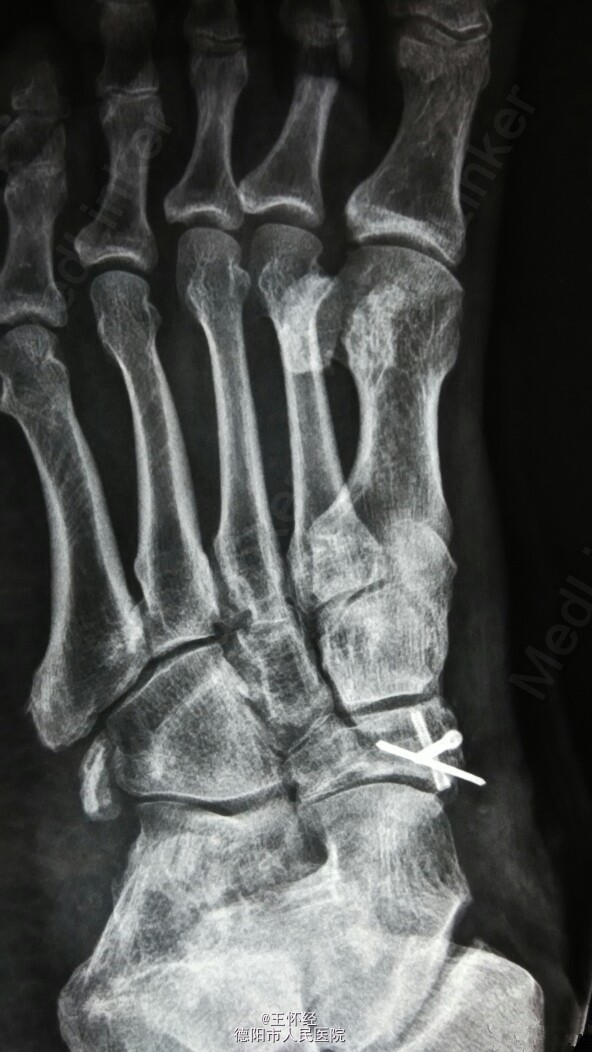

舟骨骨折

患者男性,49岁,外伤后急诊入院,发现舟骨骨骨折,行手术治疗